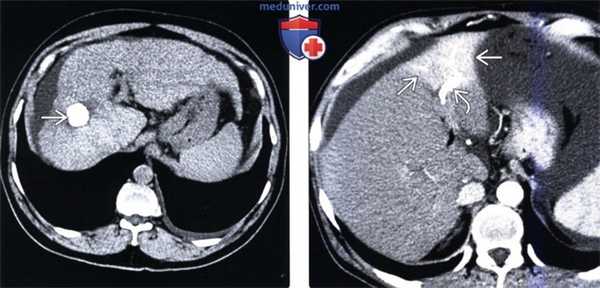

• Скопления газа в паренхиме печени или возле нее:

о Инфаркт объемного образования или паренхимы печени, обусловленный ятрогенными причинами:

- Быстрая гибель паренхимы печени (или иной ткани) с высвобождением газа, возможно, также с присоединением инфекции:

Например: радиочастотная абляция, химиоэмболизация сосудов печени, окклюзия артерий печени (как преднамеренная, так и произвольная)

- Высвобождение газа происходит при быстрой гибели ткани:

И не обязательно означает инфицирование

Клиническая симптоматика (лихорадка, боль, лейкоцитоз) может имитировать сепсис

о Абсорбируемая оксидированная целлюлоза (серджисел):

- Помещается в зону оперативного вмешательства и остается там с целью контроля кровотечения

- Выглядит как «губка» с множественными пузырьками газа и с минимальным количеством жидкости либо полным ее отсутствием:

Пузырьки газа плотно прилежат друг к другу, могут также иметь линейное распределение; стенка, накапливающая контраст, отсутствует

Локализация и вид изменений при последующих исследованиях остаются неизменными

На УЗИ выглядит как гиперэхогенное образование с артефактами, обусловленными задней реверберацией